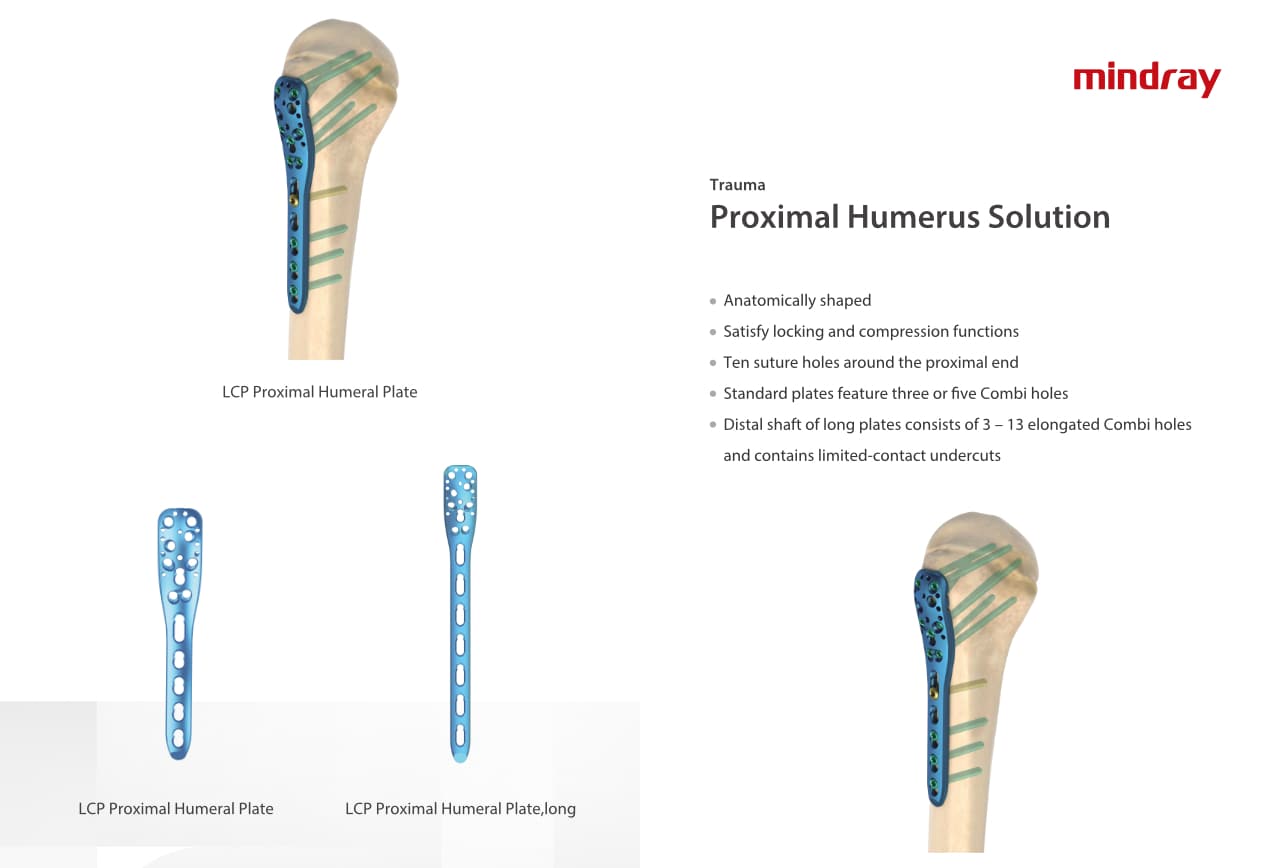

Traumatologie